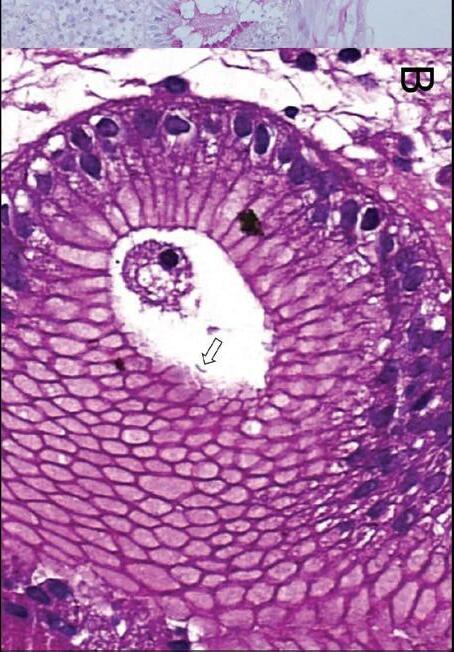

In a 1991 report in The American Journal of Gastroenterology, Drs. Alemayehu and Järnerot challenge prior orthodoxy that colonoscopy is contraindicated in patients with severe ulcerative colitis.